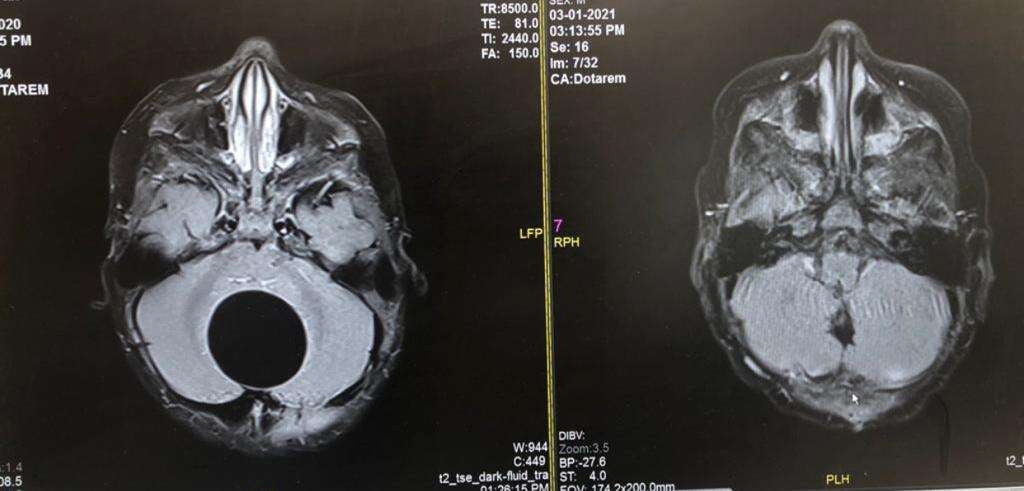

הגידול בראשו של התינוק, לפני ואחרי הסרתו // צילום: דוברות שערי צדק // הגידול בראשו של התינוק, לפני ואחרי הסרתו

הכל התחיל לפני כחודש, כשההורים הבחינו בשינוי מוזר בהיקף ראשו של התינוק ופנו לרופא בקהילה. בהוראתו פונה הפעוט לבית החולים, שם ביצעו כמה בדיקות שלא הותירו ספק - הגידול הפעיל לחץ כבד על גזע מוחו, ובשל כך הוא הועבר בדחיפות לשולחן הניתוחים בהליך חירום.

"מדובר בגידול נדיר ביותר שאנו רואים אחת לעשור. היינו חייבים לפעול מהר, כי זיהינו לחץ על גזע המוח ואגירת נוזלים שהייתה יכולה לסכן את חייו", סיפר ד"ר גוסטבו רייז, שניתח את התינוק.

עוד הוסיף: "הגידול הוצא בשלמותו בעזרת טכנולוגיה חדישה. הניתוח עבר בהצלחה ללא נזקים וחיי התינוק ניצלו. כעבור מספר ימים שחררנו אותו לביתו במצב טוב. הבדיקה הפתולוגית הראתה כי מדובר בגידול שפיר, והפעוט ממשיך להתפתח כראוי".